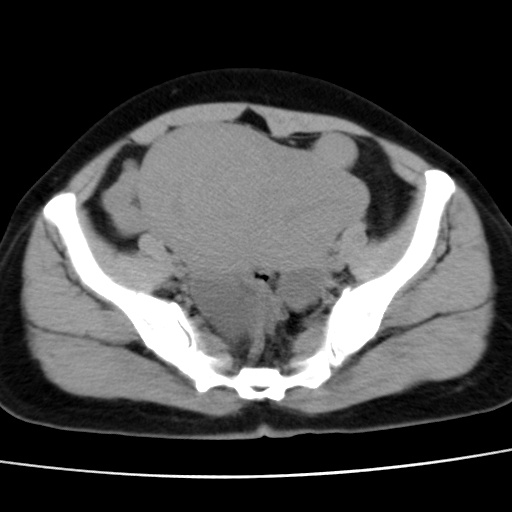

子宫多发肌瘤吗

多发性子宫肌瘤.

考虑多发子宫肌瘤,子宫直肠窝双囊性占位,另直肠周围脂肪密度增高,不知有何病史

支持考虑多发子宫肌瘤~!子宫直肠陷凹积液?

支持考虑多发子宫肌瘤~!子宫直肠陷凹积液!

子宫肌瘤,宫体部后方见液性密度影,是肠道还是子宫与直肠陷窝积液不好说,我觉得它的位置有点高

支持考虑多发子宫肌瘤!子宫直肠陷凹积液!

患者发热,而子宫直肠窝液性灶有明显边缘且局限且囊性,不除外为包裹性积液或脓肿

支持考虑多发子宫肌瘤,子宫直肠陷凹积液可能。

考虑多发子宫肌瘤

1)考虑子宫肌瘤可能性大。2)子宫后方囊性占位性病变,不排除卵巢囊肿可能。

考虑多发子宫肌瘤。子宫后方囊性占位性病变,不排除卵巢囊肿可能。